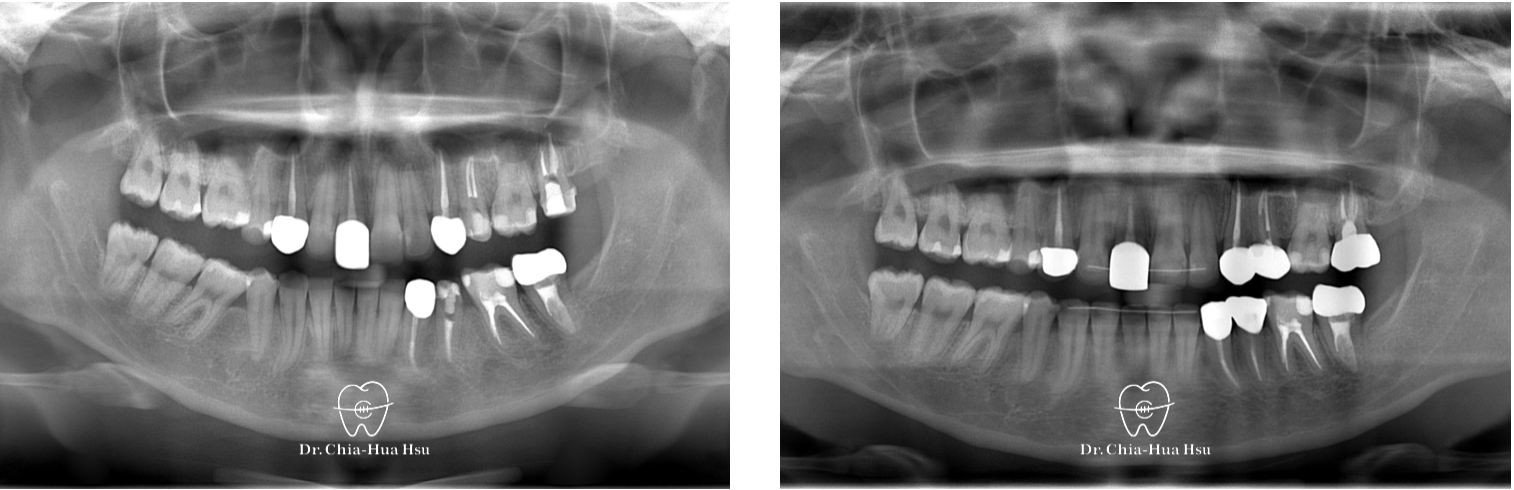

- 問題分析:患者是骨骼一類咬合(Skeletal Class I)伴隨深咬。

- 治療方式:使用傳統金屬矯正器,搭配骨釘、骨板,整平下顎咬合平面,改善深咬。另外,上顎門牙貼片也有稍作調整,恢復適當的長寬比例。

治療前

治療後